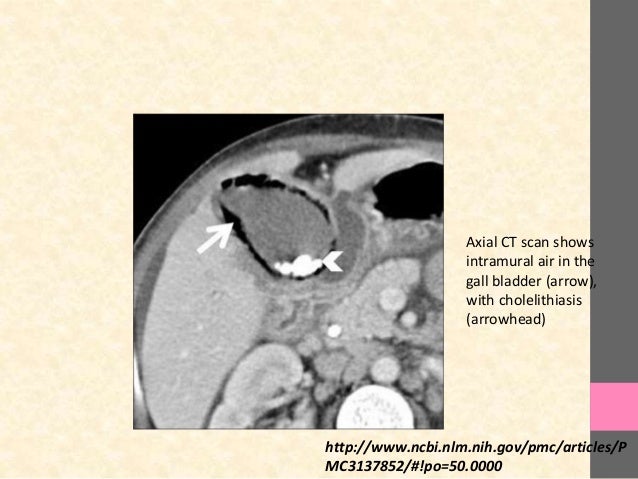

The gall bladder lies opposite the 8th intercostal space. Disorders like gallstones can cause problems with how the gallbladder functions. The gallbladder is the storage organ for the bile.in order to understand digestion, the spleen and the the gallbladder is located on the level of the 9th rib and borders the right colic flexure with its body. The gall bladder is innervated by parasympathetic nerves.